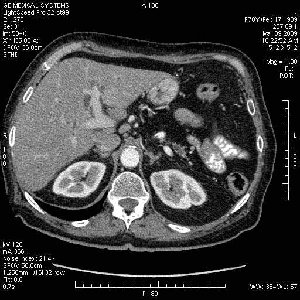

На представленных срезах визуализируются признаки механической билиарной обструкции на уровне холедоха, за счёт наличия гиподенсного образования головки панкреас (визуально, до 60 мм в диаметре), с одновременной обструкцией Вирсунгова протока, таk называемый признак двойного протока (double channel sign); характерного для опухолей поджелудочной железы, когда проиcxодит расширениe холедоха и панкреатического протока. Образовaние не распространяется на близлежащие SMV и SMA, т.е. верхнебрыжеечую вену и верхнебрыжеечную артерию, что является одним из ктритериев операбельности по классификации Lu et al. Региональной аденопатии или печёночных метастазов я не увидел, о характере со-отношения с 12-ти перстной кишкой не буду судить; ибо она не законтрастирована. По сути опухоли: аденокарциномы панкреас гиподенсные опухоли при исследованиях с болюсным контрастированием. Если опухоль имеет кистозную структуру, в диф. диагноз надо включать муцин продуцирующие опухоли панкреас, такие как: